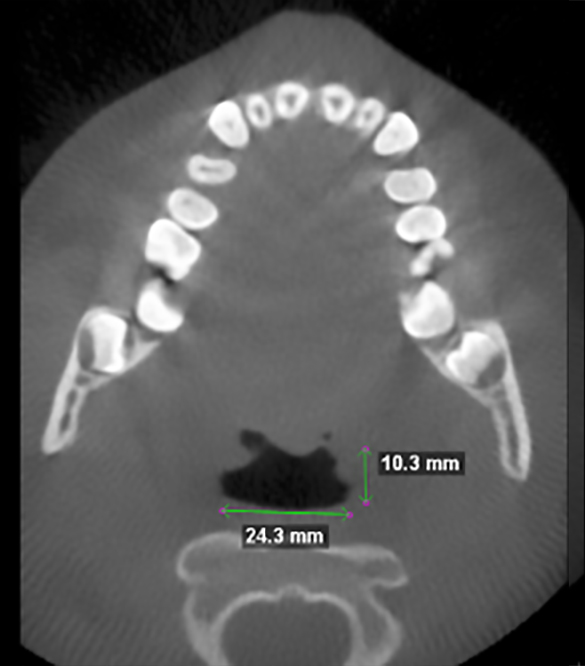

Measurements of upper airway before treatment.

Measurements of upper airway after 9 months.